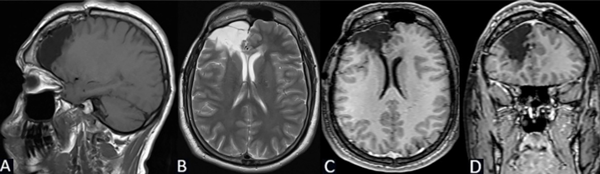

Se solicita RM de cerebro con contraste de cortes de 1 mm donde se objetiva lesión espontáneamente hipointensa en la secuencia T1 localizada en la región frontal derecha entre F1 y F2 de 3 x 2.25 x 2.84 cm. Hiperintensidad de la sustancia blanca subcortical en T2 de forma triangular con base hacia la corteza y vértice hacia la región ventricular (signo del transmanto), engrosamiento cortical focal, pobre delimitación entre la sustancia blanca y gris. Sin efecto de masa y escaso realce tras la administración del contraste (Figura 1).

Figura 1. Caso 1: RM de cerebro. A) Secuencia T1. Corte sagital. B) Secuencia T2. Corte axial. C) Secuencia T2. Corte coronal. D) Secuencia T1 con contraste. Corte axial.